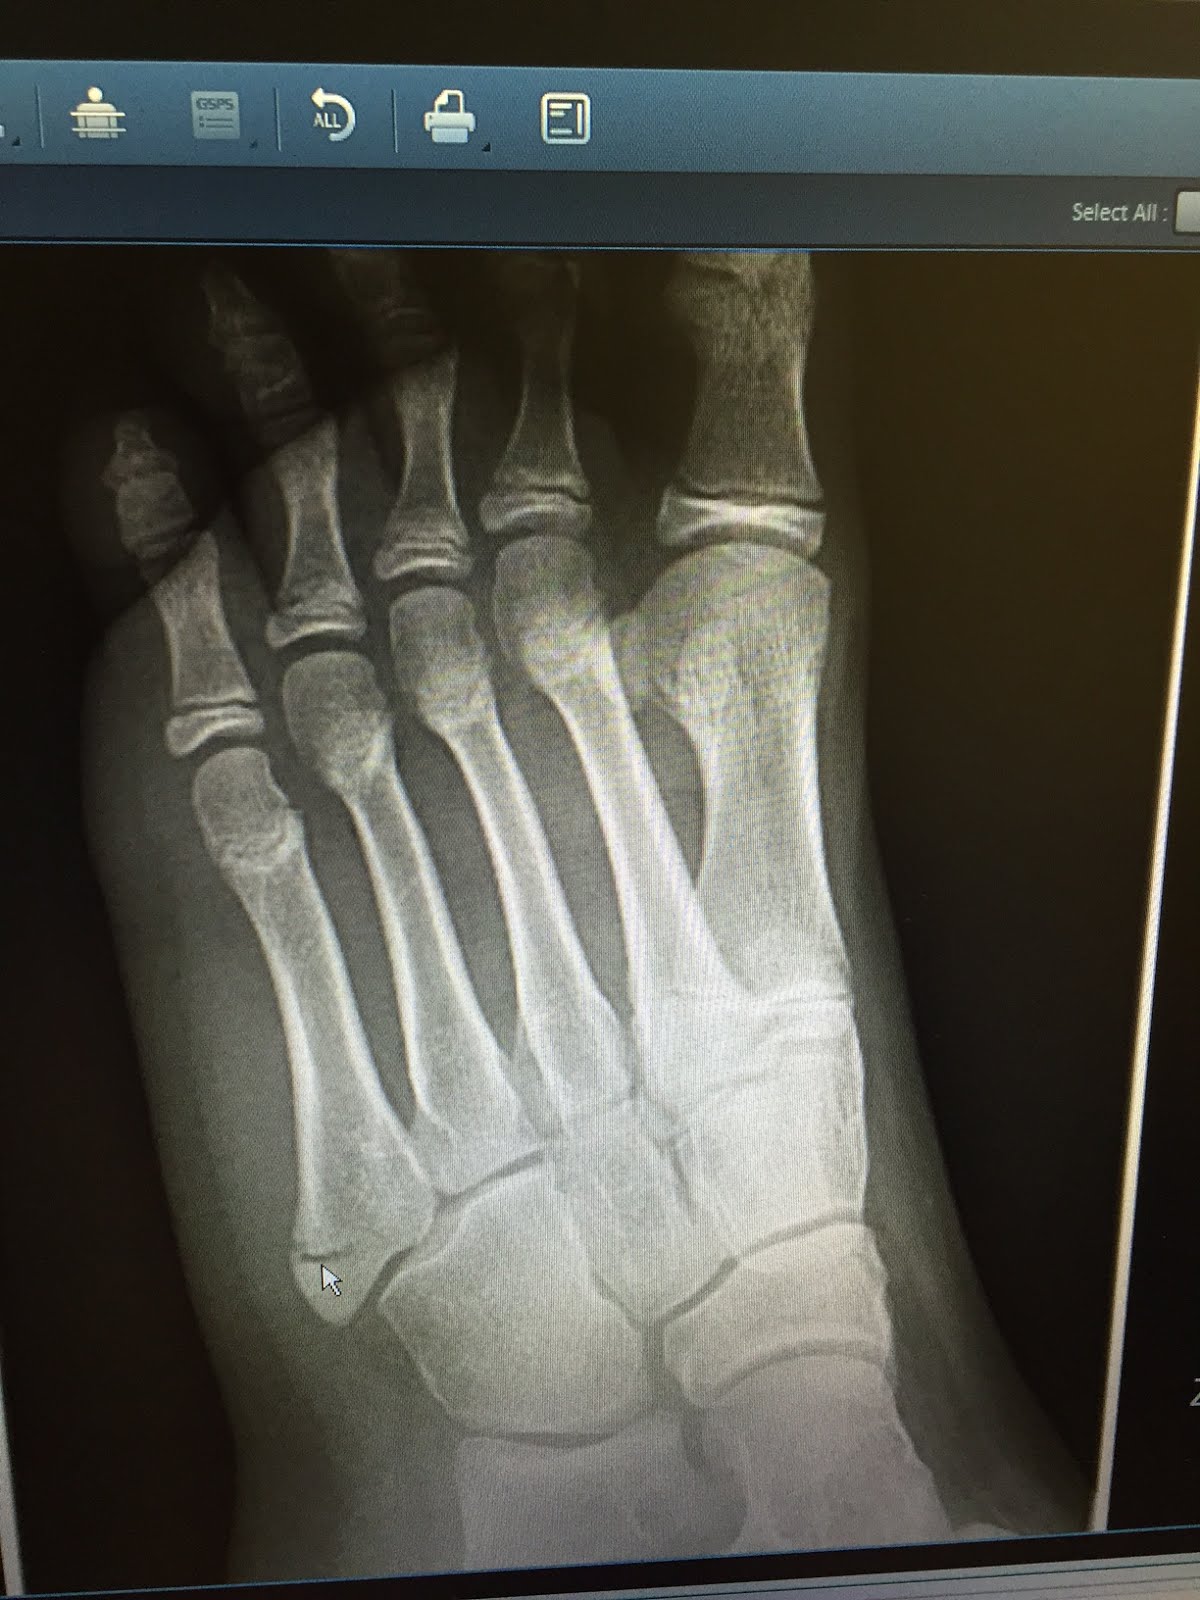

from dicasradiologia.blogspot.com

DICAS DE RADIOLOGIA Tudo Sobre Radiologia IMAGENS RADIOLÓGICAS

DICAS DE RADIOLOGIA Tudo Sobre Radiologia IMAGENS RADIOLÓGICAS Quinto Metatarso the apophysis of the proximal 5th metatarsal (plural apophyses) lies laterally and is oriented longitudinally parallel to the. una guida completa sulla frattura del quinto metatarso, le cause, i sintomi, il trattamento e la fisioterapia. scopri cos'è, perché si rompe e come si cura la frattura del 5 metatarso, l'osso più sottile e mobile del piede. Grazie. Quinto Metatarso.

Radiografía del pie que muestra una fractura del quinto metatarso Quinto Metatarso Scopri le tipologie, le complicazioni e i consigli naturali per il recupero. Leggi i tipi, i sintomi, le cause e le cure di questa lesione frequente e dolorosa. Esta fractura, ubicada en el hueso. il quinto metatarso è l'osso lungo sulla parte esterna del piede, che può fratturarsi a causa di distorsioni, cadute o traumi. scopri cos'è, perché. Quinto Metatarso.